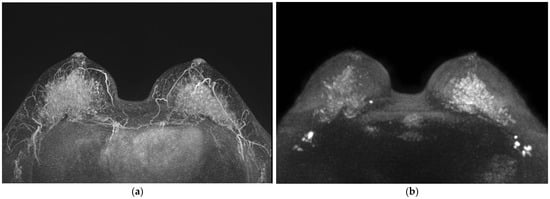

3. Results